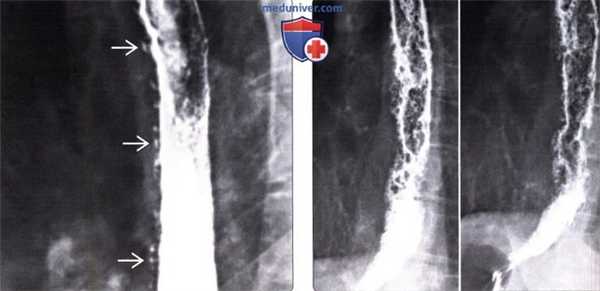

(Слева) Продольно ориентированные бляшки слизистой оболочки, характерные для кандидозного эзофагита.

(Справа) На рентгенограмме пищевода с двойным контрастированием визуализируются дефекты наполнения, расположенные продольно, которые обусловлены наличием бляшек. Рентгеноскопия с двойным контрастированием является очень точным методом в выявлении характерных поражений пищевода при кандидозе: бляшек, язв, и менее типичных проявлений кандидозного эзофагита. Тем не менее, у большинства пациентов сочетание одинофагии и кандидозного поражения слизистой оболочки рта является достаточным основанием для постановки диагноза и начала лечения. (Слева) На рентгенограмме визуализируется пищевод с неровными внутренними контурами вследствие наличия язв и бляшек, приподнятых над поверхностью слизистой. Множественные псевдодивертикулы представляют собой неравномерно расширенные выводные протоки, имеющие вид колбы с широким дном и уз -ким горлышком. Эти неспецифические изменения также могут наблюдаться при хроническом эзофагите или синдроме нарушения моторики пищевода.

Кандидозный эзофагит.

При рентгенологическом исследовании определяются дискретно расположенные дефекты наполнения в средней трети пищевода, ориентированные вертикально.

Складки слизистой оболочки утолщены (стрелки).

(Справа) На рентгенограмме пищевода с двойным контрастированием визуализируются дефекты наполнения, расположенные продольно, которые обусловлены наличием бляшек. Рентгеноскопия с двойным контрастированием является очень точным методом в выявлении характерных поражений пищевода при кандидозе: бляшек, язв, и менее типичных проявлений кандидозного эзофагита. Тем не менее, у большинства пациентов сочетание одинофагии и кандидозного поражения слизистой оболочки рта является достаточным основанием для постановки диагноза и начала лечения.